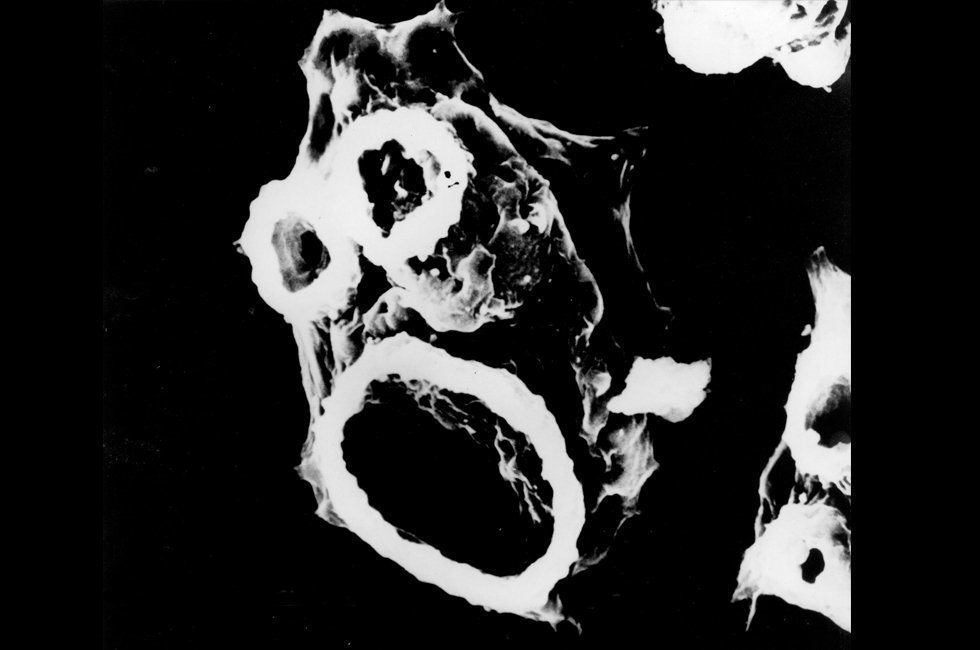

Con todos los síntomas anteriormente enlistados, los doctores ofrecieron como primer diagnóstico meningitis. Sin embargo, tras la muerte del menor, el caso fue revisado por personal de diversos hospitales y se llegó a la conclusión de que la verdadera causa de muerte fue un mal conocido como meningoencefalitis amebiana primaria (MAP). Como su nombre lo indica, los males que atacaron al niño después de sólo nadar en una laguna fueron provocados por la “ameba come cerebros”.

El que esta noticia tome relevancia se debe a que, según la Sociedad Internacional de Enfermedades Infecciosas (ISID), este es el primer caso de MAP del que se tiene conocimiento en Argentina. Aparentemente, el parásito habría ingresado al organismo del niño cuando éste se metió a nadar en las aguas contaminadas de la laguna de Mar Chiquita. La ameba se introdujo por la nariz del menor (única forma en que consigue entrar en el cuerpo humano), para inmediatamente dirigirse a su cerebro y destruir el tejido encefálico.

De las 30 especies de Naegleria la fowleri es la única que tiene capacidad de actuar como parásito. No por contagio o por beber agua contaminada, sino como sucedió con el niño argentino: la ameba se pega en las mucosas nasales y de ahí se dirige al cerebro. La infección que ocasionó la muerte de menor es poco frecuente, pero en caso de presentarse es en verano, debido a que en esa época del año las aguas son más templadas.